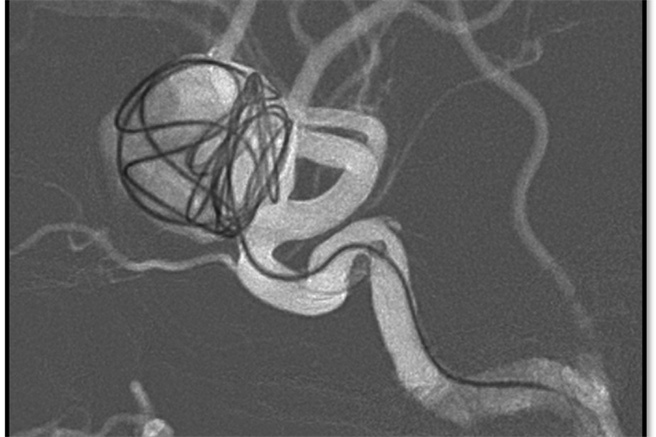

46岁的女子长期饱受头晕、胸闷症状,日前因突发性昏厥被送往台北慈济医院,被诊断出颅内有一个约2公分大的动脉瘤,最后接受线圈手术将血流导向正轨,并填塞动脉瘤空腔,肿瘤体积逐渐缩小,艾女也顺利康復;医师示警,动脉瘤就像颗不定时炸弹,严重的话可能破裂,造成颅内出血,死亡率达3成,二度破裂致死率则攀至6成以上。

常见动脉瘤大小约为0.3-0.5公分,艾女平时作息正常且无不良嗜好,慈济医院神经血管介入治疗科医师阮郁修採「血流导向装置辅助线圈栓塞术」,透过导管将缠绕的线圈放进动脉瘤的空腔,让动脉瘤内的血流停滞产生栓塞,重新把血流引导到正常的血管;数据显示,此类手术成功率达9成以上,术后半年8成的动脉瘤就会栓塞,术后三年98%的动脉瘤完整栓塞。